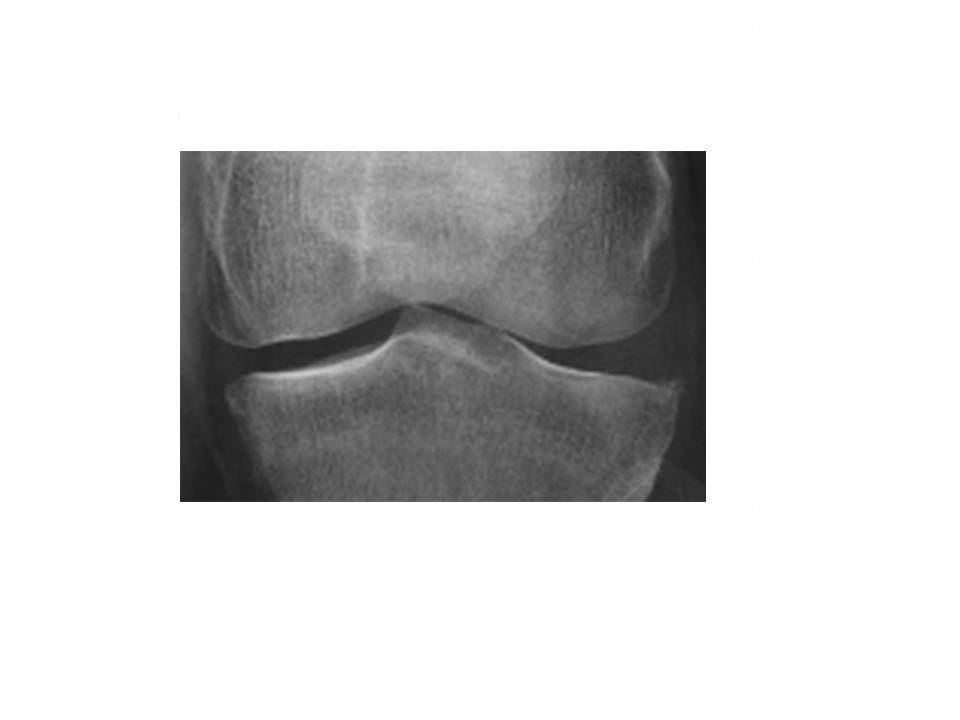

Il s’agit d’une ostéophytose du genou gauche. Gonalgie gauche interne avec ostéophytose sans pincement du compartiment fémoro-tibial interne.